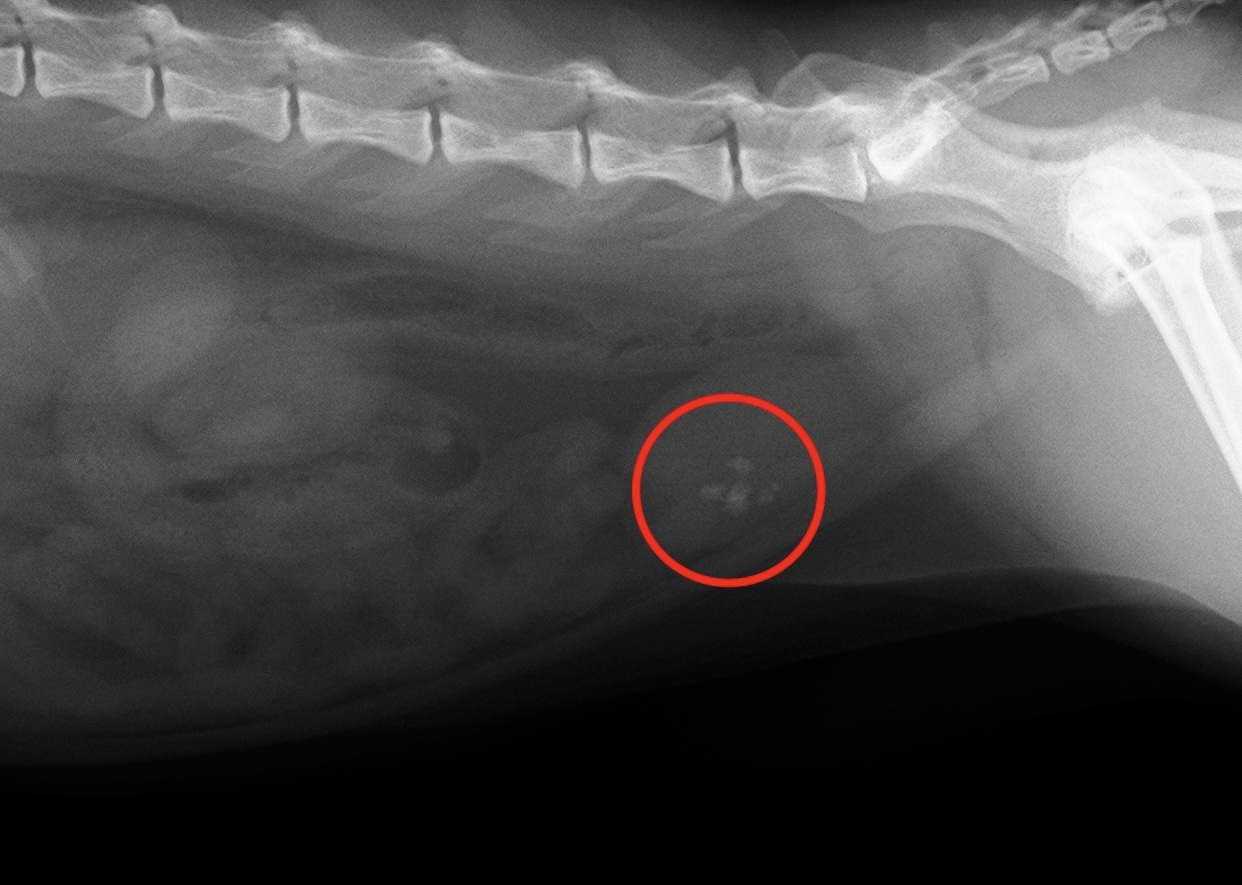

②X線検査

結石の有無、結石の大きさの確認、腎臓や膀胱の大きさなどを確認します。

【5歳去勢済みの猫 膀胱内に結石】

X線検査ではっきり見える結石がある場合、シュウ酸カルシウムの可能性が高く、この結石は解けないため外科手術が必要になります。